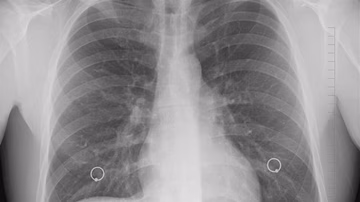

"Nije točno da se od sutra može doći na pretrage za rano otkrivanja raka pluća" Vijesti | 16. sij. | 0

Kreće program otkrivanja raka pluća, poziv na pregled svima iz rizične skupine Vijesti | 12. ožu. | 0